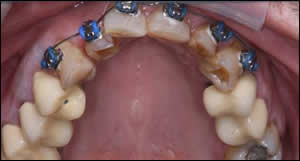

Fig 8: The maxillary anterior teeth were slenderized and orthodontic appliances were inserted.

Fig 9: Nickel titanium wires with Tip-Edge brackets provided rapid leveling and unraveling of the incisors with light force.